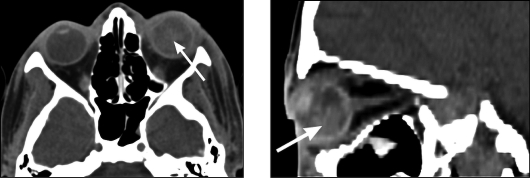

(рис. 3).

Рис. 3. Рентгенограммы глазного яблока с

протезом Комберга-Балтина (тонкая стрелка) в боковой (а), аксиальной (б)

проекциях. Инородное тело глазницы (толстая стрелка)

Рентгенография по методике Комберга-Балтина: для

определения их внутри-или внеглазного расположения проводят

рентгенофункциональные исследования с выполнением снимков при взгляде вверх и

вниз (см. рис. 3).